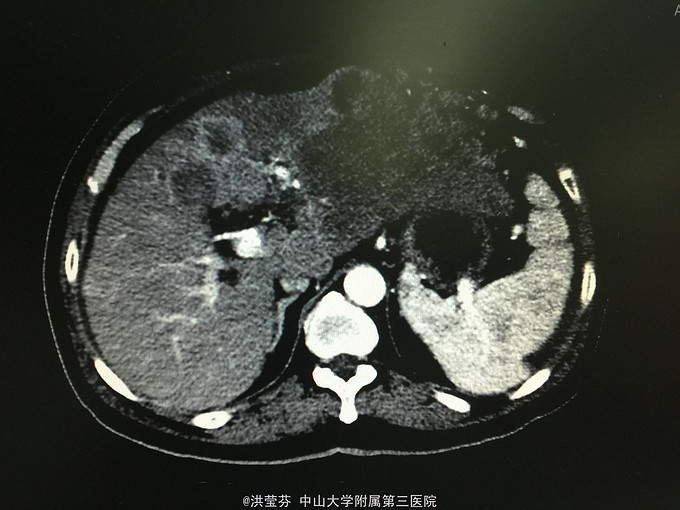

查体:上腹部轻压痛,无反跳痛。 辅助检查:上腹部CT增强提示:肝S2/3/4段恶性肿瘤,肝内多发子灶,肝左静脉及门静脉左、右支受侵;腹腔多发转移瘤;肝门部、腹膜后多发肿大淋巴结;门静脉海绵样变;少量腹水。胸部CT提示:1、双肺多发小结节,结合病史,考虑转移瘤;纵膈、双侧肺门多发肿大淋巴结。2.双肺炎症;左侧胸腔少量积液。CA125 555.1IU/nl,CA199 1093.5IU/nl。

诊断考虑胆管细胞癌可能性大,予完善肝穿刺,活检病理示:符合中分化腺癌,胆管细胞癌可能性大。免疫组化结果示:Hep(-),CK(+),CK19(+),CEA(-),CDX-2(-),DK20(-),Ki 67(约15%),TTF-1(-)。诊断明确肝内胆管细胞癌,IV期,无明显化疗禁忌,予GP方案化疗,辅以护胃、护肝、止吐等治疗。